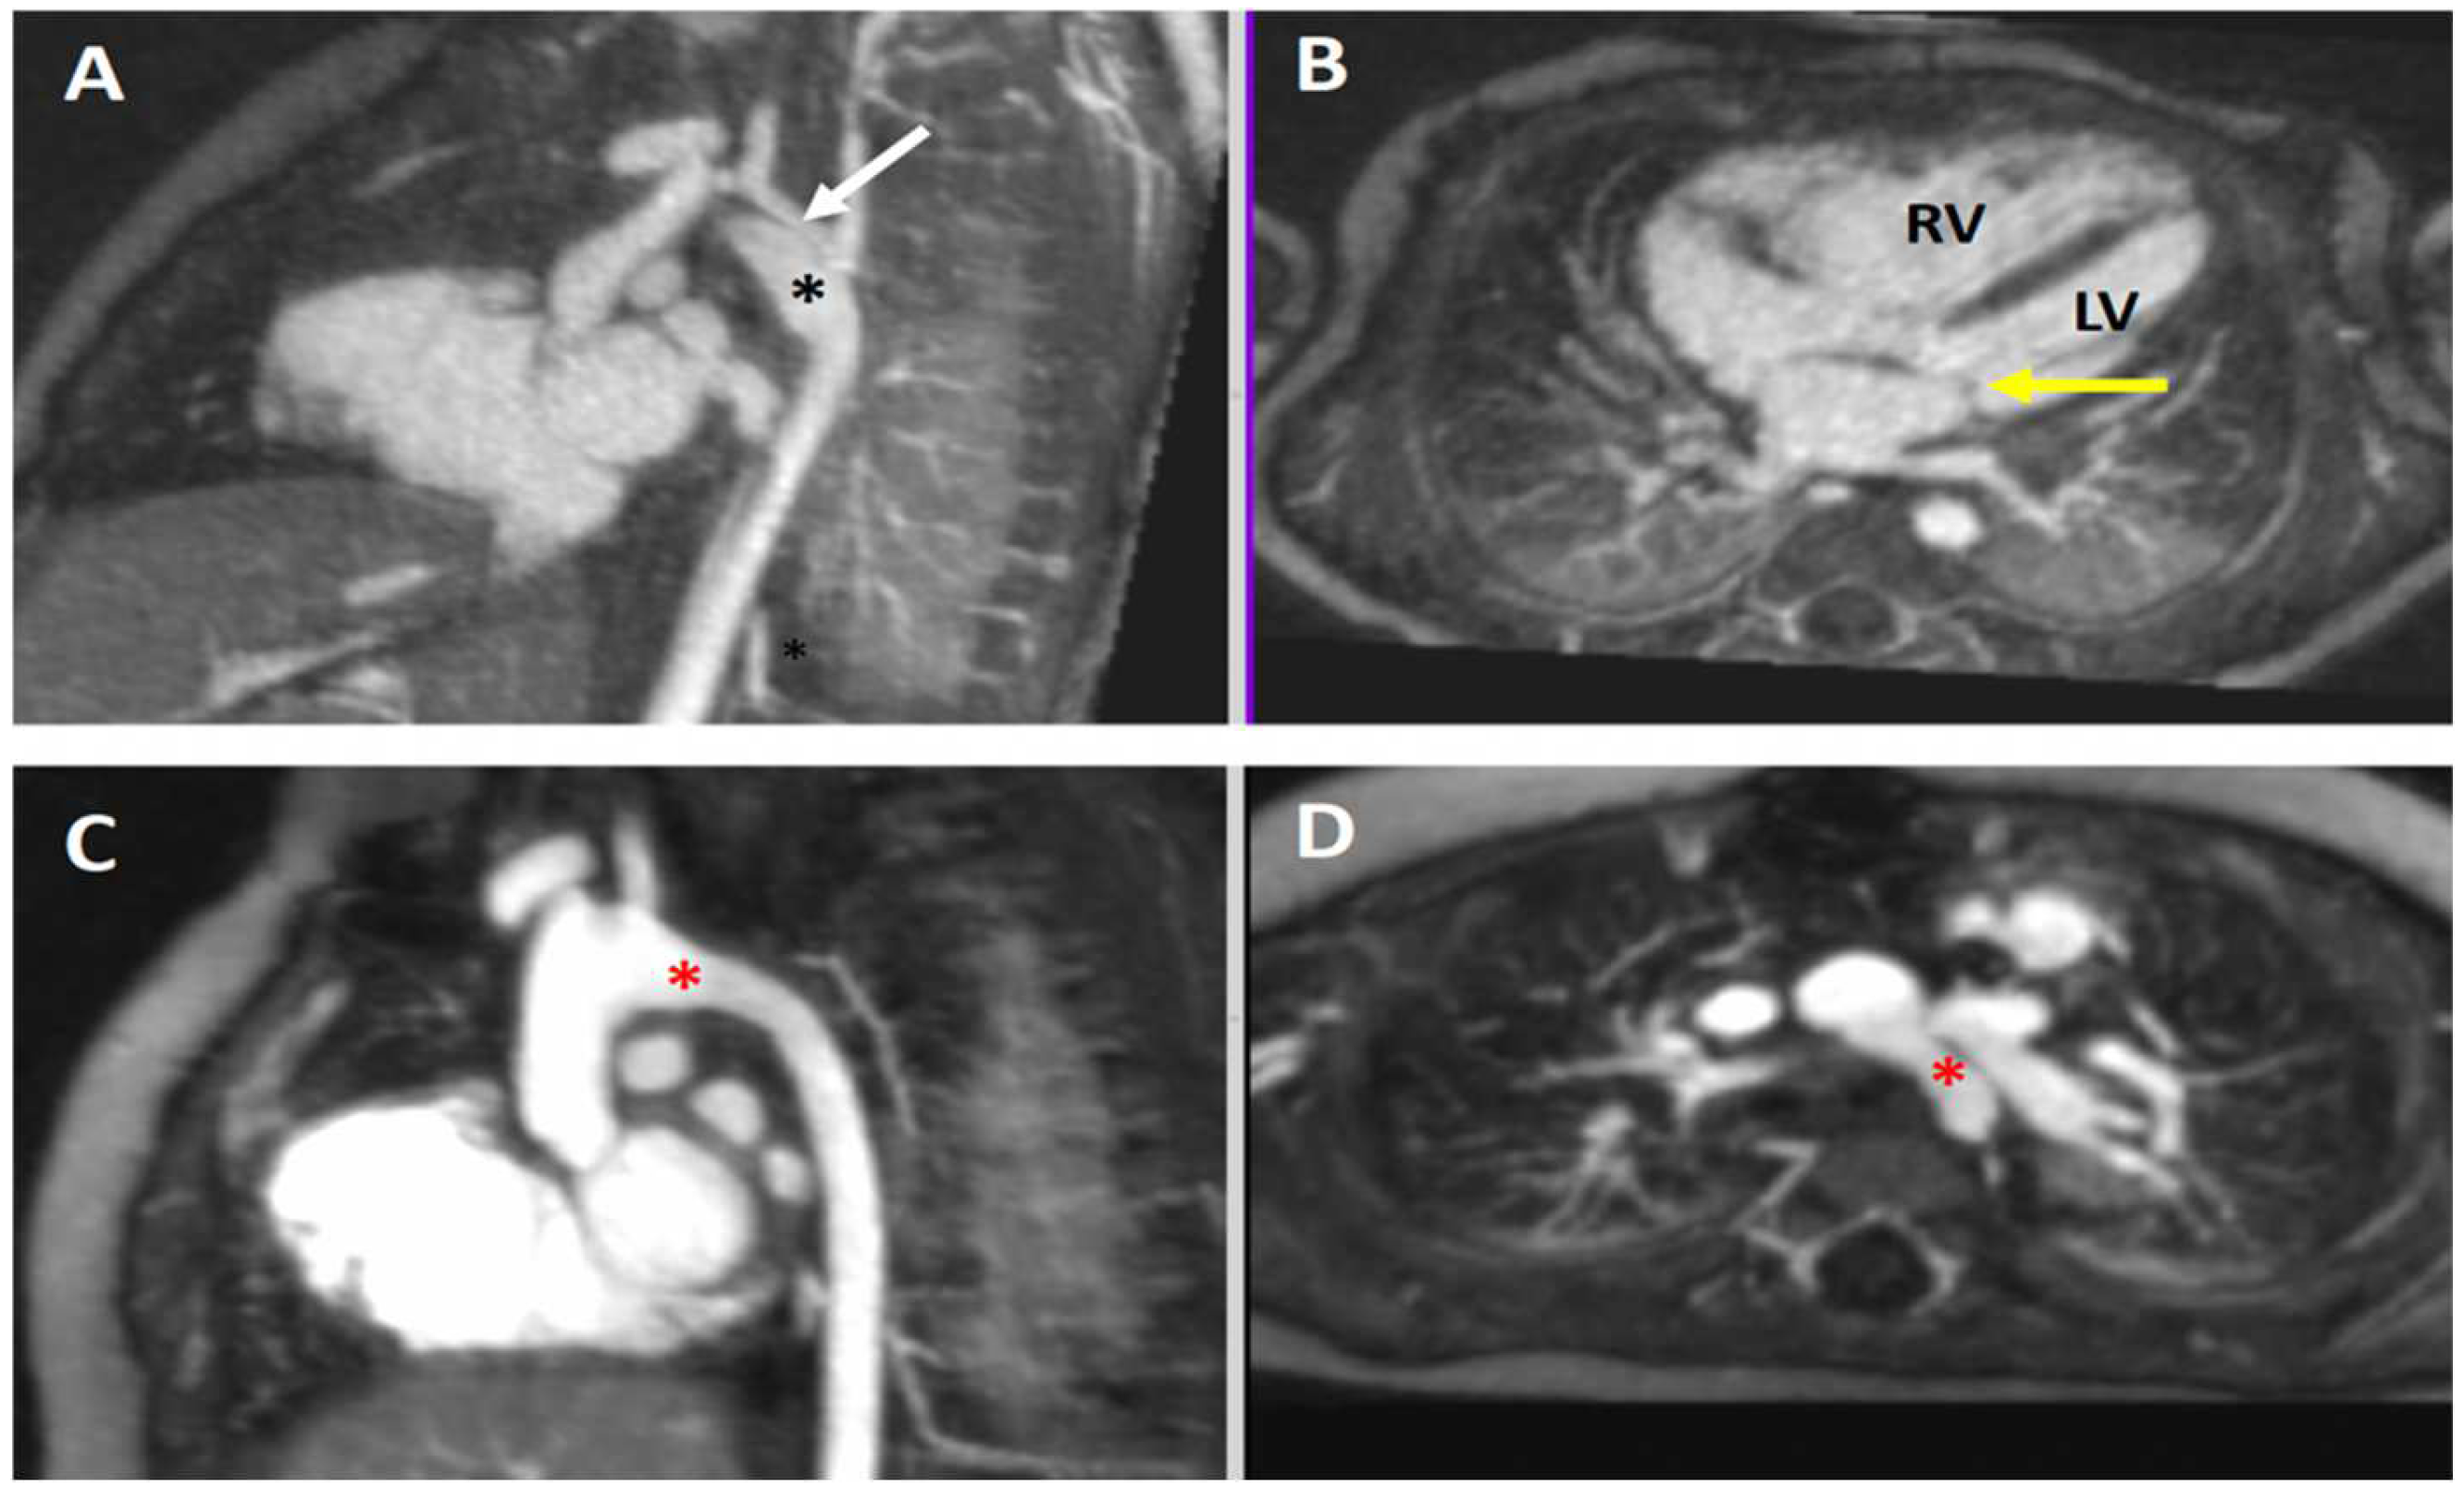

4.3.1. Coarctation of the Aorta

4.3.2. Aortic Aneurysm in Connective Tissue Disease

4.3.3. Vascular Ring

4.3.4. Pulmonary Atresia in Tetralogy of Fallot